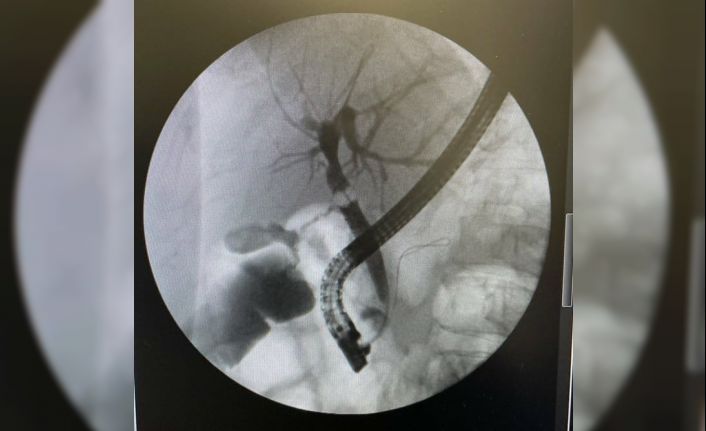

Safra yolları, karaciğer ve pankreas hastalıklarının tanı ve tedavisinde kullanılan ERCP işlemi Ağrı Eğitim ve Araştırma Hastanesi’nde ilk kez uygulandı. Gastroenteroloji Uzmanı Dr. Bayram Yeşil ve ekibi tarafından başarılı bir şekilde gerçekleşen uygulama sonucunda safra yollarında taş bulunan hasta ERCP işlemi uygulanarak sağlığına kavuştu.

Ağrı’da yaşayan 84 yaşındaki S.S hasta karın ağrısı şikayeti ile hastaneye başvurdu. Yapılan tetkikler sonucunda safra yollarında ki taşa bağlı pankreas bezi hasarı tespit edildi. Hasta hastaneye yatırılarak tedavi altında alındı ve hastaya ERCP yapılarak safra yollarındaki taş endoskopik olarak çıkarıldı. İşlemi gerçekleştiren Gastroenteroloji Uzmanı Dr. Bayram Yeşil; " ERCP işlemi Türkiye’de belli merkezlerde yapılmaktadır. ERCP, Safra yolları, karaciğer ve pankreas bezinin bir takım hastalıklarında tanı ve tedavisinde kullanılan ileri gastroenterolojik işlemlerden biridir. Endoskopik olarak gerçekleştirilen bu işlemde, ameliyata gerek kalmadan hastanın safra yollarına girilerek işlemler yapılmakta ve safra yollarında ki taşlar temizlenmektedir. Safra yollarında taş bulunan hastamızın safra yollarını temizleyerek başarılı bir işlem gerçekleştirdik. Hastamızın servisteki takibi devam etmektedir. Şu anda bu işleme ihtiyacı olan 6 hastamızın servis takipleri devam etmektedir ve bu hastalarımızın da safra yollarında ki taşlar ERCP ile temizlenecektir. Daha önce bu hastalarımızı çevre illere sevk etmek zorunda kalıyorduk. Bugünden itibaren hastalarımızı sevk etmeden işlemlerini hastanemizde yapacağız. ERCP işlemi için teknik ihtiyaçlarımızın hızlıca tamamlanmasını ve bu işlemin hastanemizde yapılmasını sağlayan başta il sağlık müdürümüz Dr. Öğr. Üyesi Coşkun Daharlı’ya, başhekimimiz Opr. Dr. Cengiz Kazdal’a ve hastane yönetimimize teşekkür ederim” dedi.